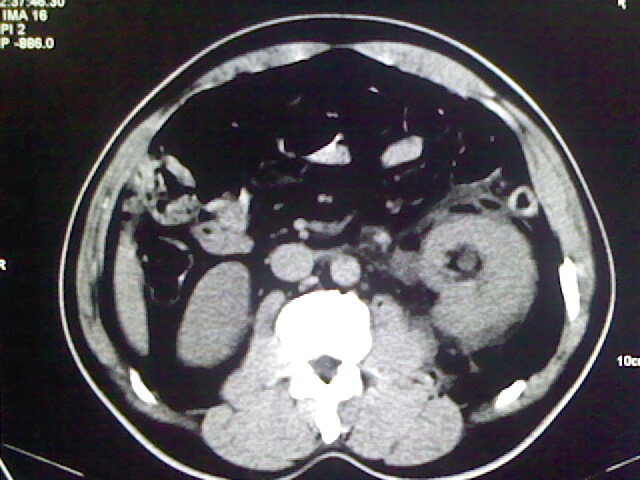

以下是引用zsl6918在2009-2-7 7:29:00的发言:[br]请提供介入的方式方法,肾及输尿管改变考虑与介入损伤有关,漏了,尿液外渗。

以下是引用余辉在2009-2-7 8:27:00的发言:[br]可能是硬化剂烧穿囊壁进入肾盂输尿管了,尿漏。不除外介入或碎石术后合并感染[br]患者术后怀疑结石,接着就碎石了?就怀疑没有确诊吗?碎石用的什么方法?气压弹道还是体外超声?如果这样的话责任人都难找

以下是引用随光逐影在2009-2-7 8:46:00的发言:[br]支持3楼意见。[br]另:不排除左肾及肾周感染可能。